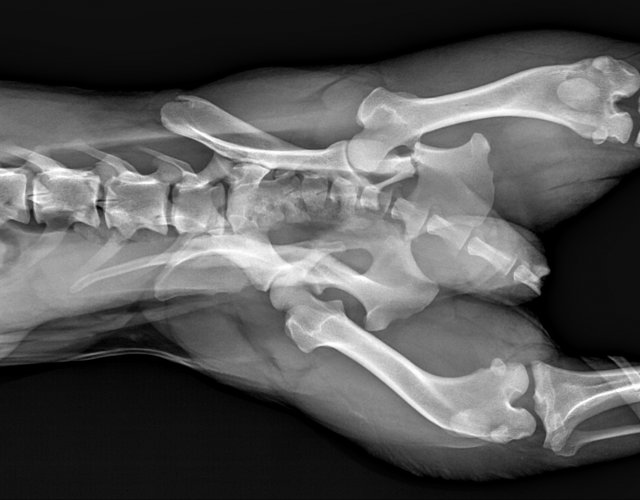

Caine accidentat

O doamna a gasit un caine lovit de masina si l-a tras pe marginea drumului pentru a suna peste tot in cautare de ajutor. Am raspuns pozitiv si am facut totul pentru el. Din pacate nu a putut fi salvat, decedand a doua zi dupa interventia chirurgicala. Foarte probabil din cauza unei embolii pulmonare. Le multumim celor care au donat. Medicul a anulat factura iar banii vor ajuta desigur alte animale de care ne ocupam zilnic.